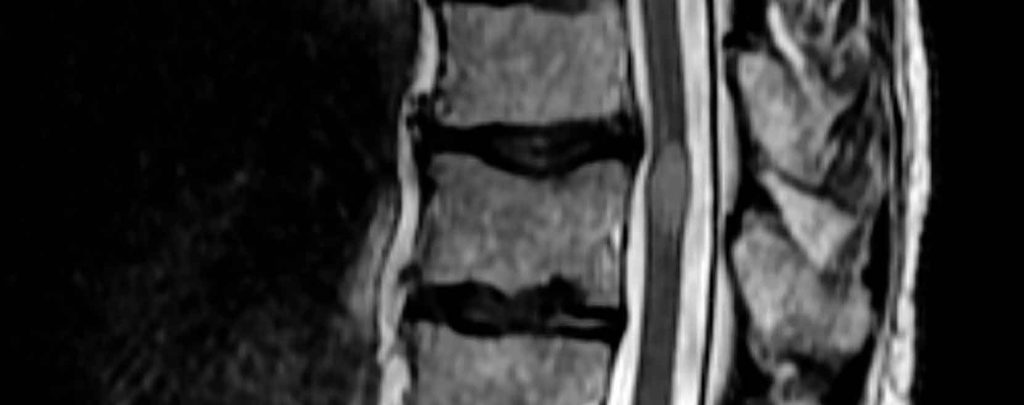

Diagnóstico por Imagen

Las imágenes para la lesión medular deben realizarse urgentemente. Los criterios NEXUS son  muy sensibles para descartar lesiones cervicales significativas sin realizar estudios radiológicos, por lo que es clave realizarlo al pie de la cama de tu paciente. En toda sospecha de lesión medular traumática en adultos debes realizar una TAC siguiendo la evaluación de la regla canadiense de la espina dorsal ó hay una fuerte sospecha de lesión de la columna vertebral torácica o lumbosacra asociada con signos o síntomas neurológicos anormales. Si después de la TC hay una anomalía neurológica que podría atribuirse a lesión de la médula espinal, realizan RM.

La tendencia actual es el realizar TAC con reconstrucción sagital y coronal. La TAC helicoidal,  permite la identificación de fracturas que pueden pasar desapercibidas en la radiología simple, proporciona una visualización completa de toda la columna con reconstrucciones que permiten caracterizar mejor la invasión de canal, facilita información con vistas al tratamiento quirúrgico.